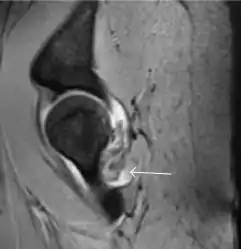

Synovial chondromatosis can be confidently diagnosed by X-ray when calcified cartilaginous chondromas are seen. However, other synovial proliferative processes, such as pigmented villonodular synovitis, require MRI for accurate diagnosis, although noncalcified synovitis can be suspected in radiographs by indirect signs, such as soft tissue swelling and/or erosions in the femoral head, femoral neck, or acetabulum (Figure 7).[1]

Figure 7:

Axial CT image of pigmented villonodular synovitis eroding the posterior cortex of the femoral neck.[1]

Sagittal T2* gradient echo image showing a posterior soft tissue mass with hypointense areas secondary to hemosiderin deposition.[1]

In synovial proliferative disorders, MRI demonstrates synovial hypertrophy. In the case of PVNS, characteristic foci of low signal intensity related to hemosiderin deposition are better seen on gradient echo T2* images (Figure 7). In the case of synovial osteochondromatosis, the synovial hypertrophy is accompanied by intermediate signal cartilaginous loose bodies and/or low signal calcified loose bodies.[1]